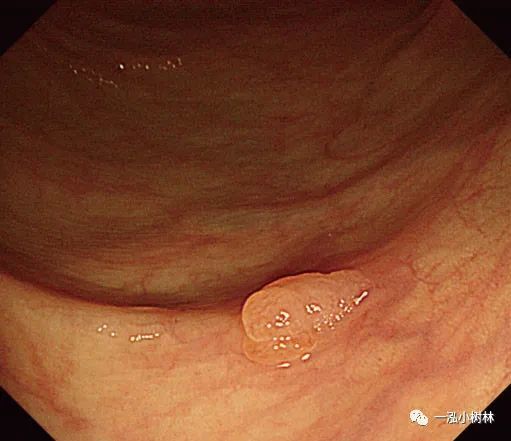

二、冷圈套息肉切除术

1.冷圈套息肉切除术(Cold snare polypectomy,CSP)是一种安全、有效的内镜下切除小息肉(小于10mm大小)的方法,但这一技术是理想的适应证是4~6mm大小的无蒂息肉。CSP与电切法相比,不存在潜在的穿孔风险。大小在10~13mm的圆形隆起息肉完全适合CSP。

图4a 小无蒂息肉的冷圈套息肉切除术

图4b 直肠5mm大小Is型无蒂腺瘤